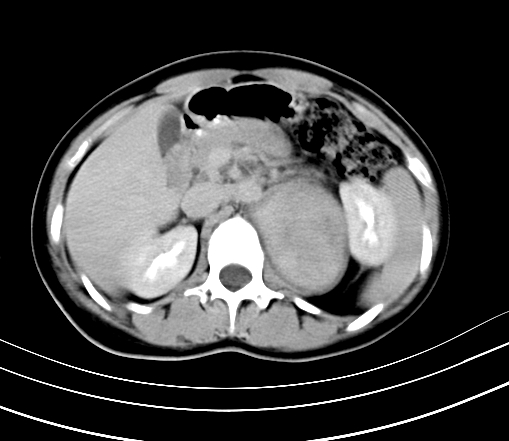

静脉期